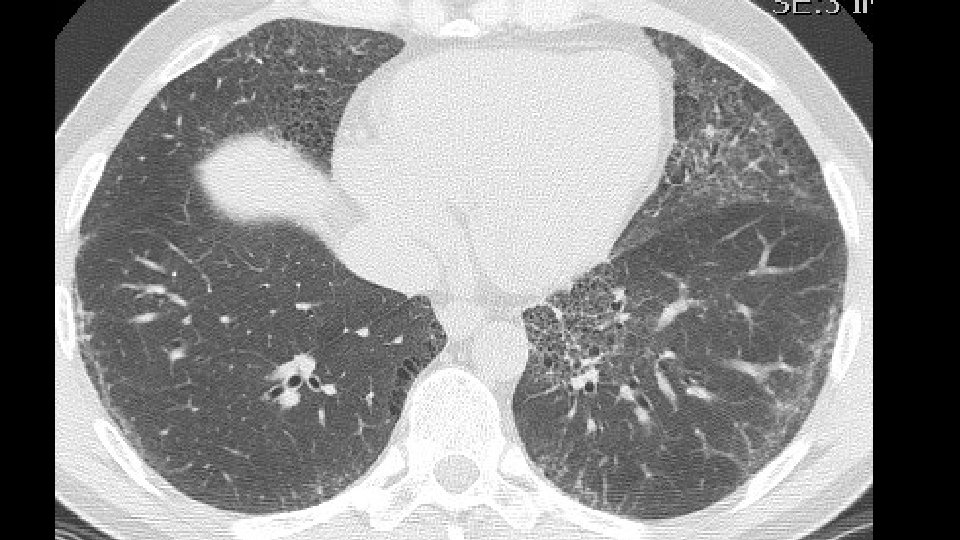

43 years old, male non smoker Co-morbidities: psoriasis, gastritis with Helicobacter History of two years of dyspnea on exertion Lab tests: no autoimmunity

Bronchovascular ground glass attenuation + subpleural sparing D. D. f. NSIP vs inconsistent UIP (GG and bronchovascular distribution)

Patients underwent transbronchial lung biopsy with cryoprobe